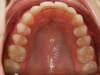

Cas 5 : Description

Absence congénitale des incisives latérales supérieures. Appareils fixes pour créer l’espace nécessaire à la mise en place de facettes en remplacement des latérales.

Après